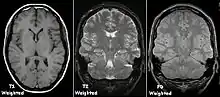

Cada tecido retorna ao seu estado de equilíbrio após a excitação pelos processos independentes de T1 (spin-tretice) e T2 (spin-spin) de relaxamento. Para criar uma imagem ponderada em T1, a magnetização pode ser recuperada antes de medir o sinal MR, alterando o tempo de repetição (TR). Esta ponderação de imagem é útil para avaliar o córtex cerebral, identificando tecido adiposo, caracterizando lesões focais e, em geral, para obter informações morfológicas, bem como para imagens pós-contraste. Para criar uma imagem ponderada em T2, a magnetização pode decair antes de medir o sinal MR alterando o tempo de eco (TE). Esta ponderação de imagem é útil para detectar edema e inflamação, revelando lesões de substância branca e avaliando a anatomia zonal na próstata e no útero.

| Eco de spin | Ponderado em T1 | T1 | Medição da relaxação spin-lattice usando um tempo de repetição (TR) curto e tempo de eco (TE) curto. |

| Ponderado em T2 | T2 | Medição da relaxação spin-spin usando TR e TE longos |

![]() | |